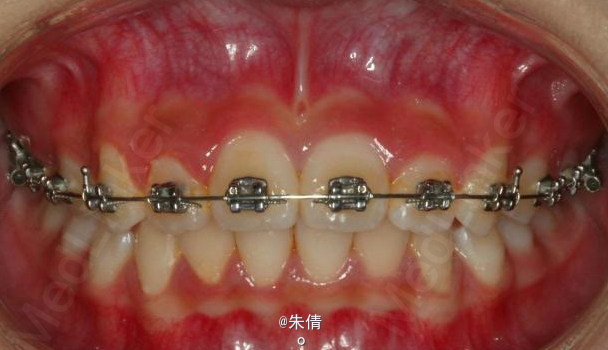

对于面型较好,拥挤度不大的病例,推磨牙向后不失为一种很好的方法,当然现在推磨牙后向的手段和方法很多,但是主要 是适应证的问题。我认为我们在做推磨牙向后,首先是考虑拥挤度,第二个要考虑的是现有的面型,第三点也是很重要的一点,是考虑牙弓后段拥挤度,Tweed-Merryfireld拥挤度的诊断方法将牙弓拥挤度分析分为三段,牙弓前段拥挤度,牙弓中段的拥挤度,以及牙弓后段的拥挤度。不管用什么方法或是手段推磨牙向后,一定不能将牙弓前端矛盾移到牙弓中段或是后段。今天给大家看一直面型,拥挤度不是很大推磨牙向后的病例。希望对大家能有所帮助。